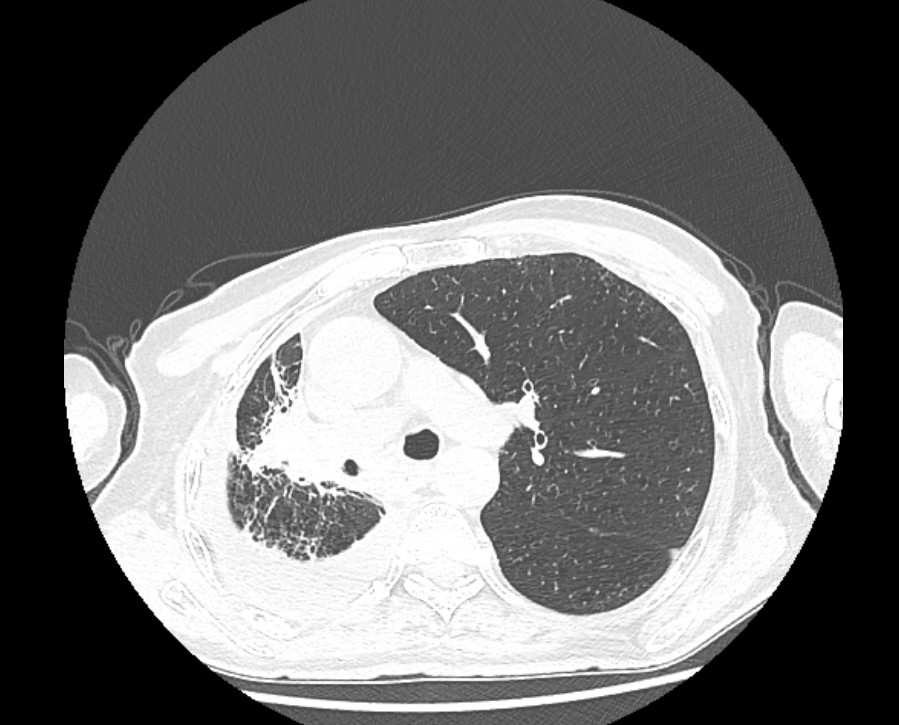

2023年7月18号上午,广西中医药大学附属瑞康医院空港院区心血管内科团队联合本部重症医学科一区ECMO团队运用ECMO(体外膜肺氧合)技术顺利为一...